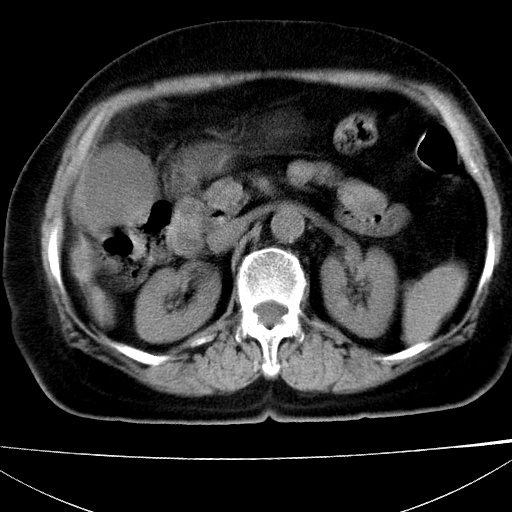

患者女74岁;右上腹胀痛1月,伴恶心,无发热;生活在疫水区。有术后病理及术后半年的追踪ct.

1)慢性血吸虫病(典型)。2)肝硬化。3)肝癌?4)胆囊炎。5)少量腹水。6)右侧少量胸腔积液。

肝脏体积缩小,肝裂增宽,边缘不平呈波浪状,肝右叶见分隔状条索形钙化,亦见多结节低密度灶,边界不清,肝周可见少许液性暗区,胆囊增大内密度均匀,脾脏下缘低于脏脏的下缘,胸腔亦见液性暗区,余未见明显异常.

诊断:1肝硬化并慢性吸血虫病,脾肿大

2肝内占位,考虑肝癌可能性大,建议做增强

3胆囊炎, 4少量腹水及胸水

病人以胆囊癌手术的,病理结果为中分化腺癌。

现在看看肝右叶内圆形低密度影你们考虑什么呢?

肝内圆形低密度影考虑扩张的胆管

请看3mm重建像如下: